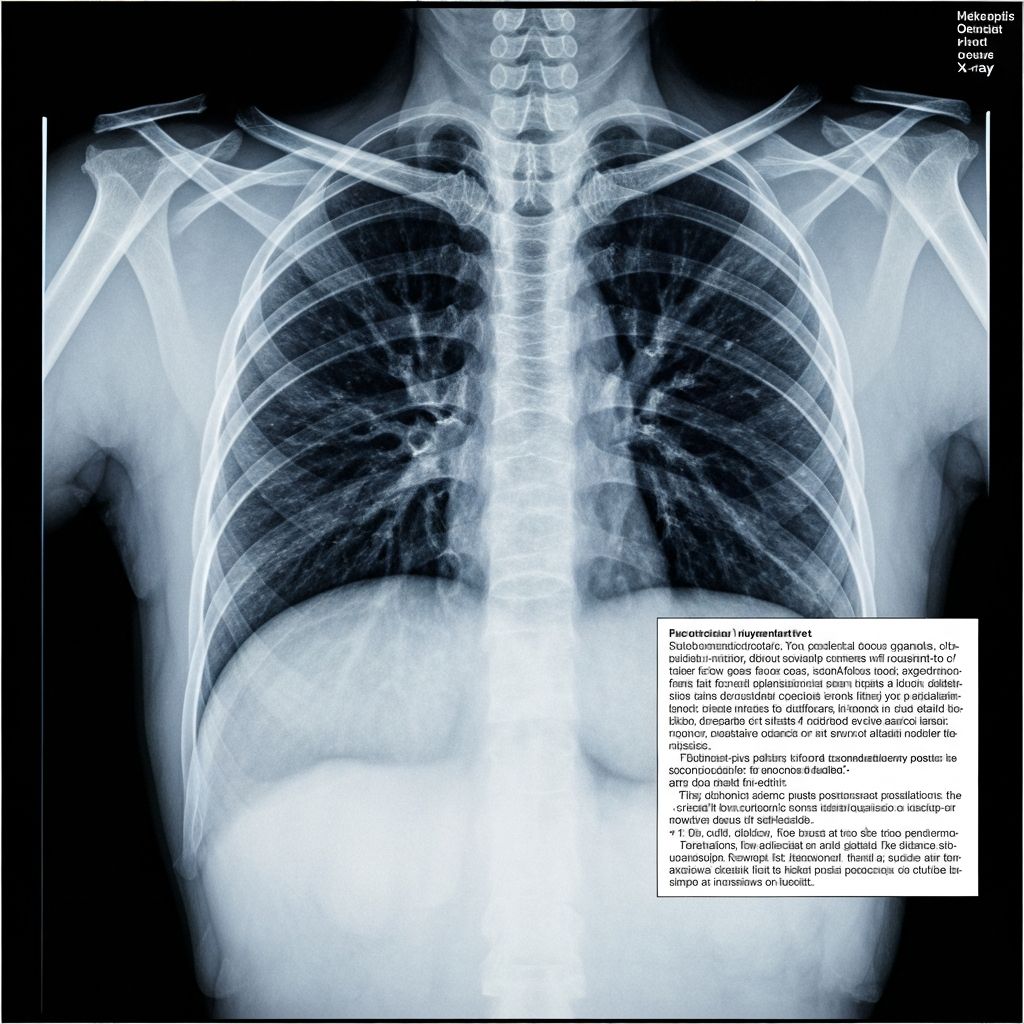

- •흉부방사선 소견(직업환경의학 전문의 소견 필수), 폐기능 검사 결과가 핵심

2. 흉부방사선 1/0 이상의 진폐병형 또는 이와 동등 이상의 소견이 있는 경우